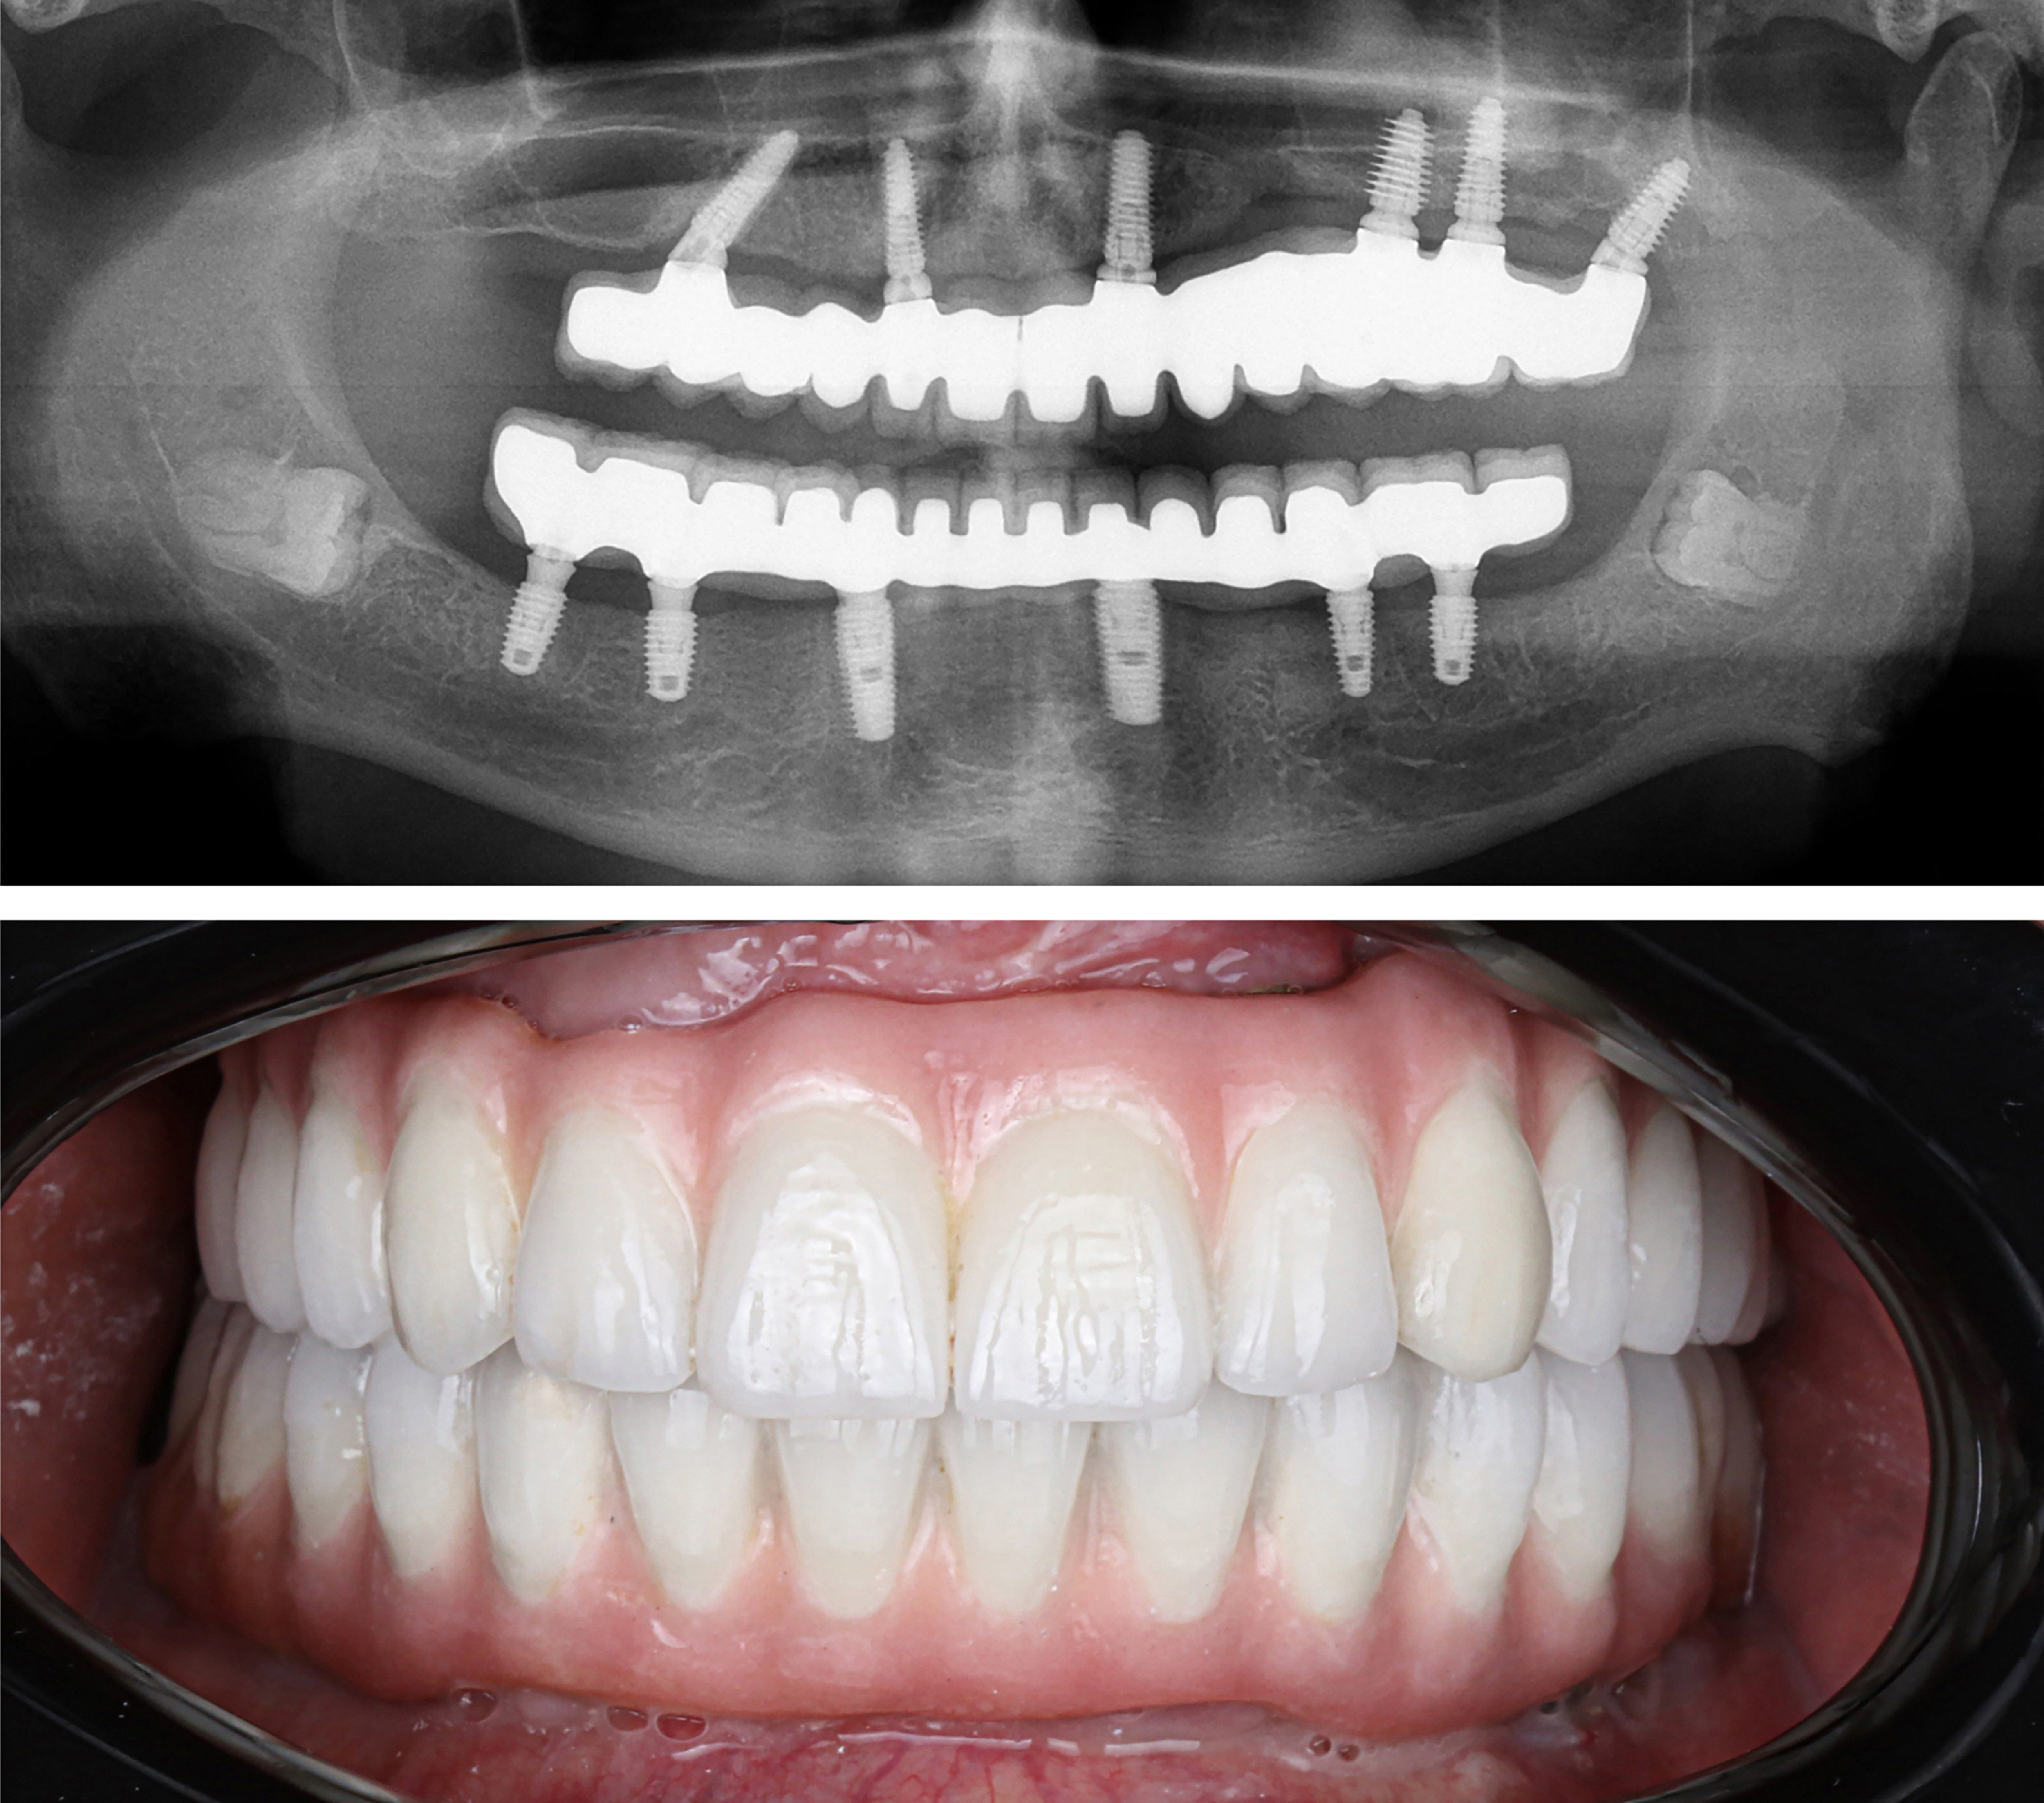

Example transformations achievable with dental implants

Starts as low as $9,999. Can Be Financed $175/mo*

Includes everything from start to finish. No hidden fees.

Includes extraction of all remaining damaged teeth. ($4000 Value)

Includes local sedation for FREE. ($2500 Value)

Includes surgical placement of 4 to 6 implants.

Includes healing teeth.

Includes final ultra aesthetic teeth.